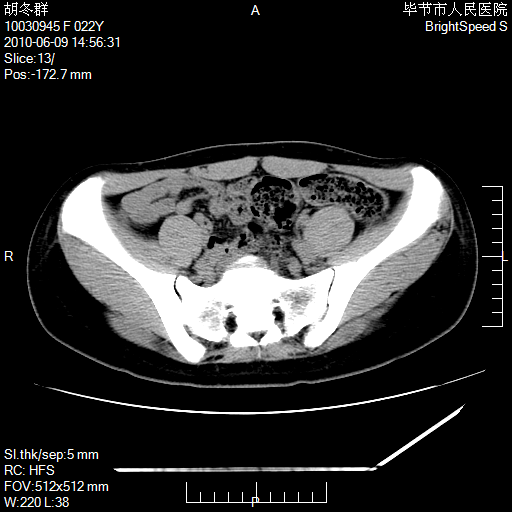

患者23岁,发现腹部包块3月。

盆腔内囊性占位;穿刺或者直接手术拿掉即可,不必紧张。

盆腔内囊性占位性病变;考虑左侧卵巢囊腺瘤。

有分隔、壁薄,支持考虑左侧卵巢囊腺瘤。

左侧卵巢浆液性囊腺瘤。

有分隔、壁薄,支持考虑左侧卵巢囊腺瘤。排尿后,膀胱缩小,由于重力作用,肿块下移就到了膀胱位置,很好理解。